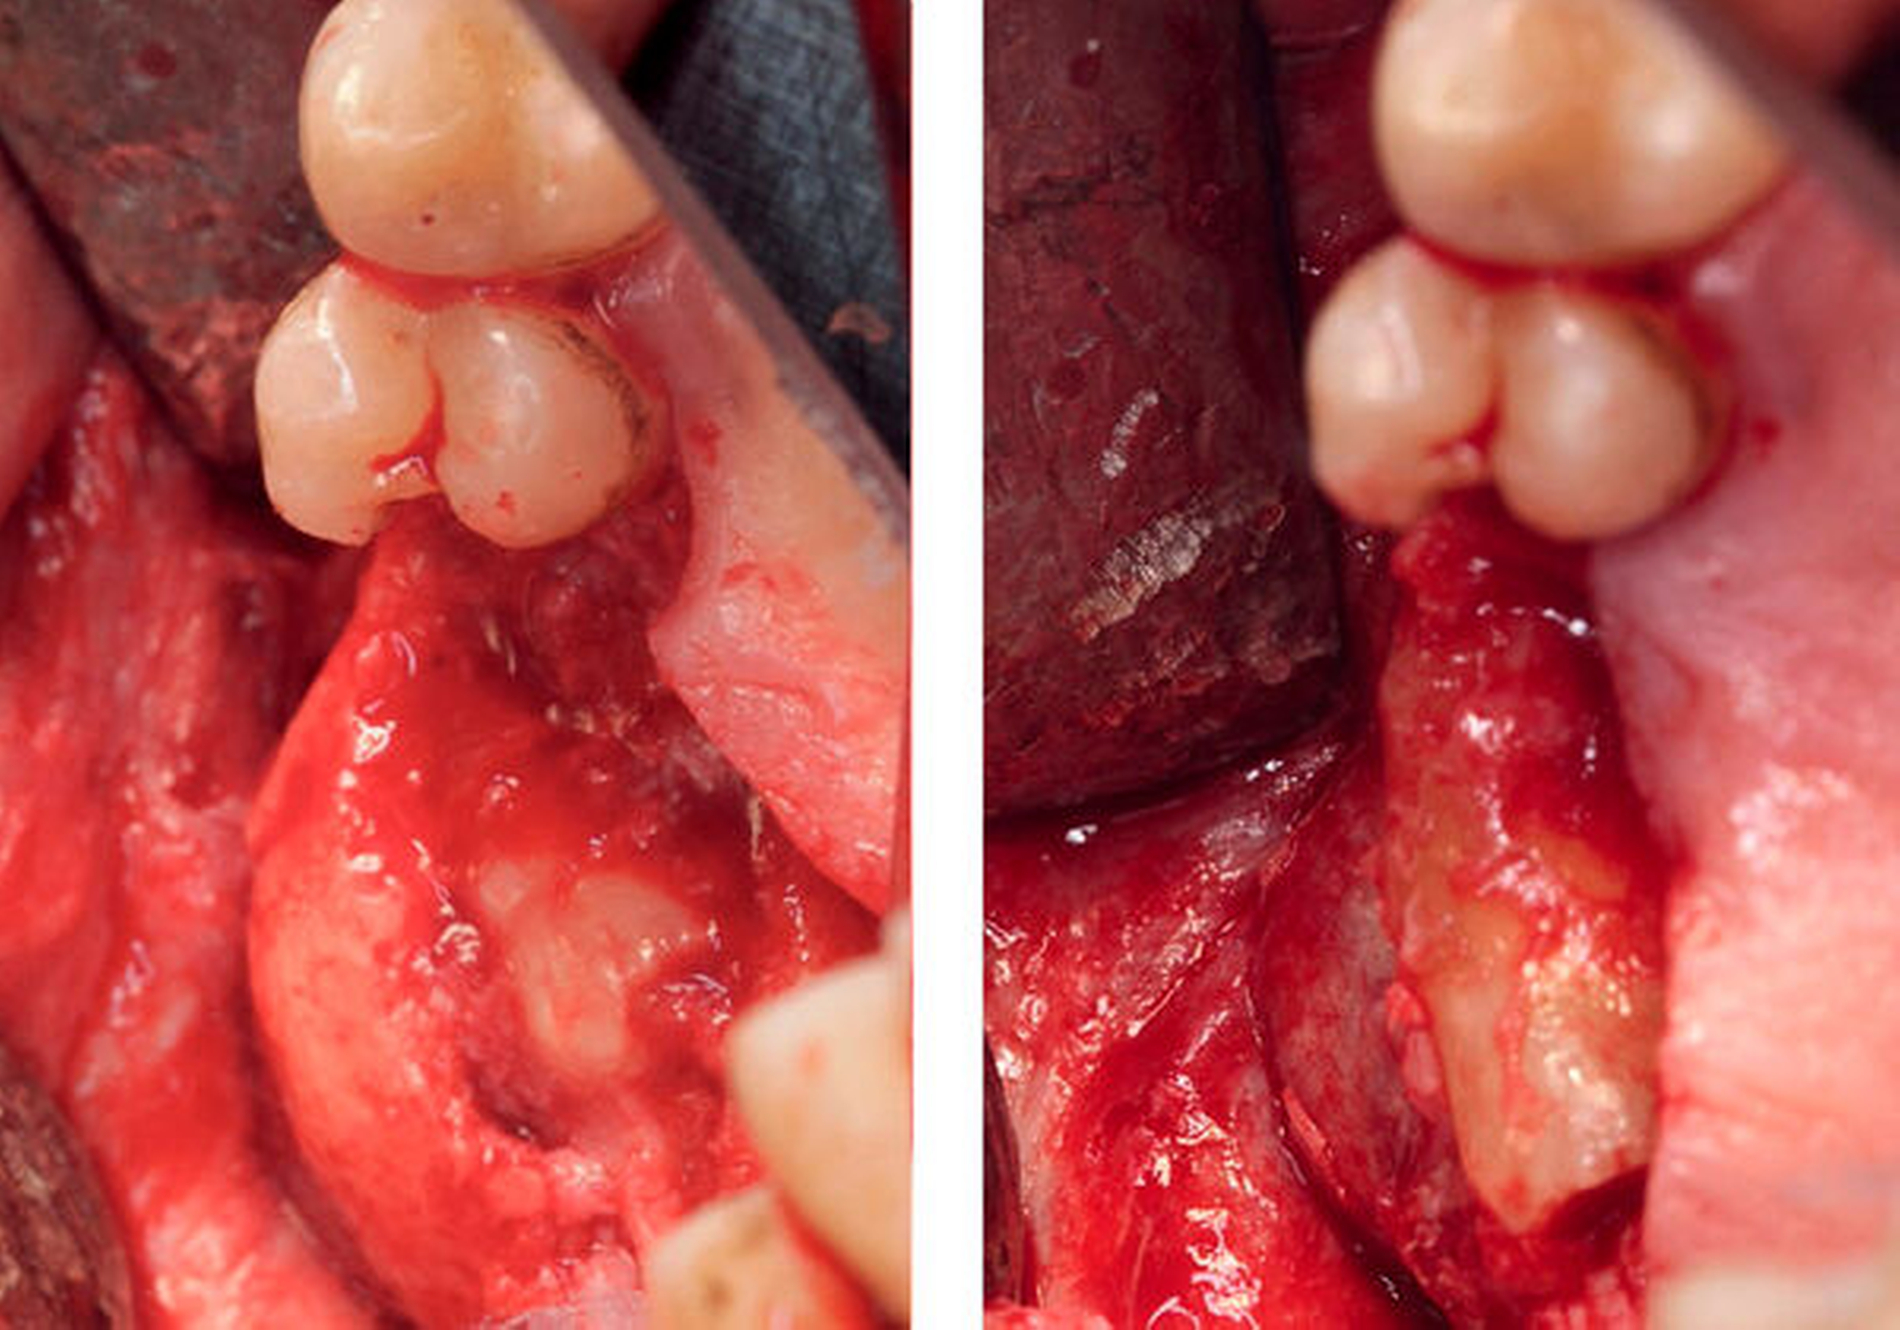

Dieser Befund wurde gemeinsam mit den retinierten Zähnen 17 und 18 mit der Verdachtsdiagnose einer follikulären Zyste in Intubationsnarkose entfernt. Nach crestalem Schnitt und Bildung eines Mukoperiostlappens war bereits die zystische Raumforderung durch den sehr dünnen Knochen sichtbar (Abbildung 4). Nach Osteotomie und Bildung eines Zugangs in die Kieferhöhle wurden die Zähne 17 und 18 mit dem umfassenden Gewebe in toto entfernt und zur histologischen Auswertung in die Pathologie gesandt (Abbildung 5). Die obere knöcherne Begrenzung des Zystenlumens wurde entfernt und somit eine Verbindung zur Kieferhöhle geschaffen. Eine Infundibulotomie war aufgrund des weit offenen Meatus nasi medius nicht notwendig. Schlussendlich wurde die Kieferhöhle unter Zuhilfenahme des Corpus adiposum buccae (Bichat’scher Fettkörper) mehrschichtig plastisch gedeckt (Abbildung 6).